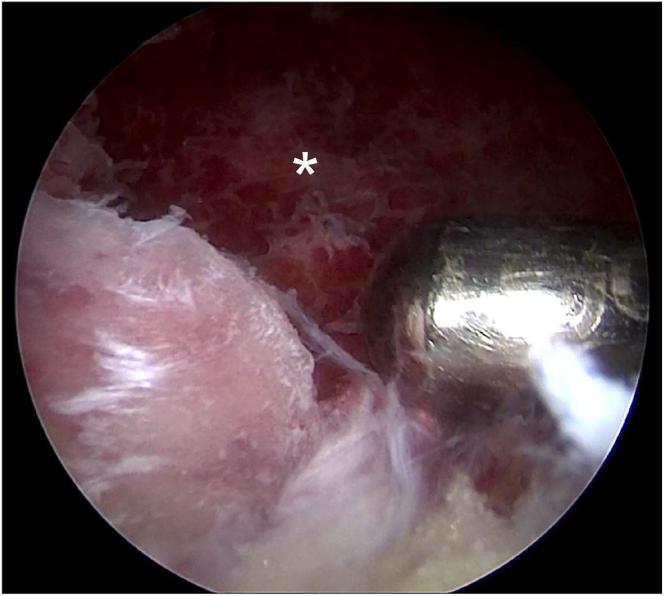

Few cases of anterior cruciate ligament (ACL) tibial avulsion injuries occur in adolescents. Bony ACL avulsion from the tibial side has been treated by various methods ranging from conservative management to a wide range of operative procedures. Various arthroscopic operative procedures are available to reduce and fix these fractures. We describe a technique of arthroscopic "8" knotted fixation without any tibial tunnels for tibial-sided ACL avulsion. This simple technique avoids the potential complications of hardware fixation within a joint. It represents an arthroscopic treatment option for ACL tibial avulsion injuries.

青少年前交叉韧带(ACL)胫骨撕脱伤的病例很少见。从保守治疗到广泛的手术操作,胫骨侧ACL骨撕脱伤有多种治疗方法。有多种关节镜手术可用于复位和固定这些骨折。我们描述了一种关节镜下“8”字打结固定技术,用于胫骨侧ACL撕脱伤,无需任何胫骨隧道。这种简单的技术避免了关节内硬件固定的潜在并发症。它代表了一种治疗ACL胫骨撕脱伤的关节镜治疗选择。